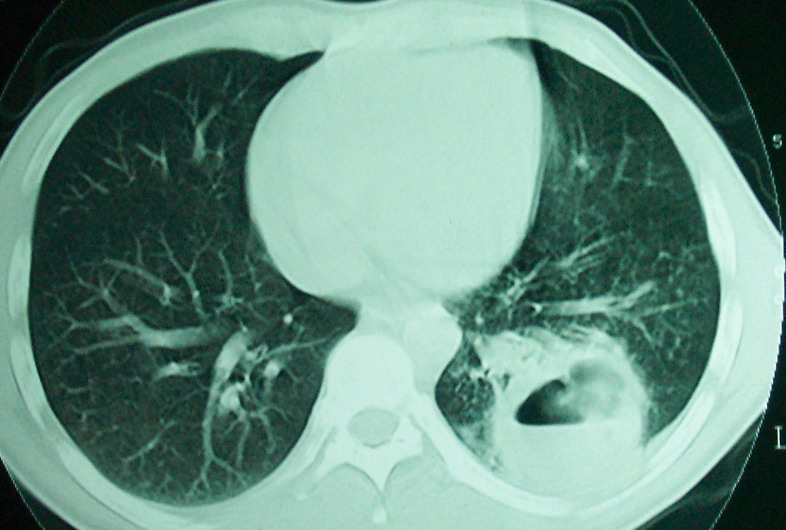

空洞内可见小结节样密度影考虑合并真菌感染

左下肺病灶除了明显的厚壁空洞 气液平外,明显见壁结节,另两肺多发小结节,综合考虑:左下肺周围性肺癌伴肺内转移.

除了肺内多发结节和左肺下叶的浓疡病灶,还应注意满肺散在的小结节影,还有右上肺前段支气管内膜不光整这些细节,结合病史,肺内多发结节应考虑结核性肉芽!